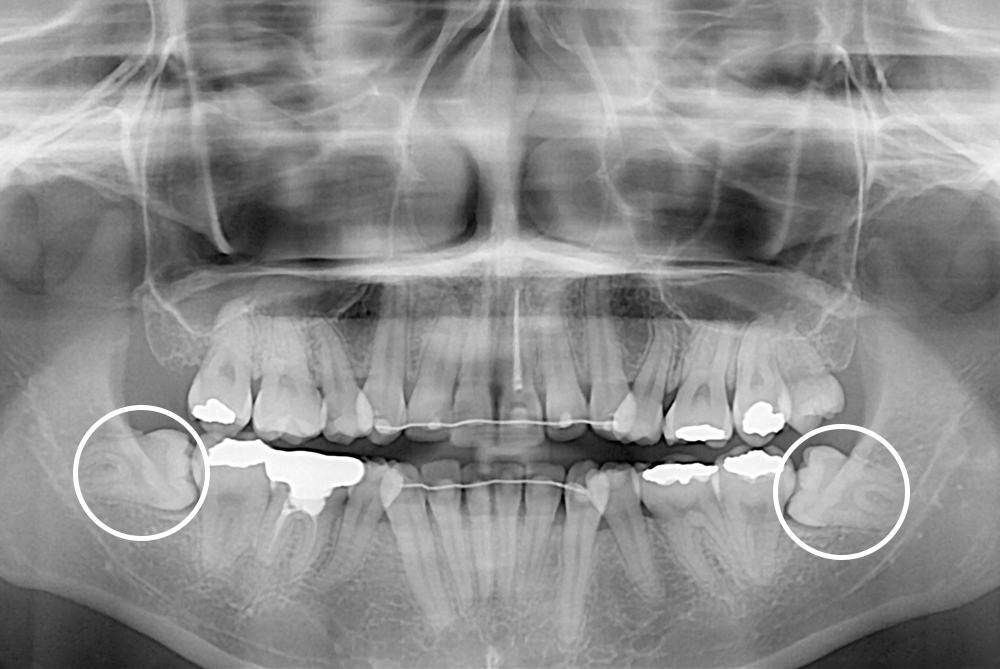

[사랑니] 매복 사랑니 발치

치료전 : 2020-06-11